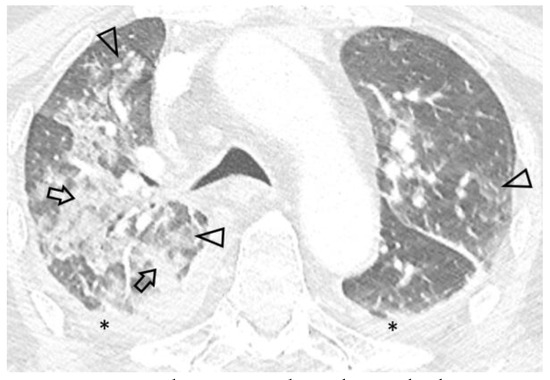

Introduction: Intravesical Bacillus Calmette-Guérin (BCG) instillation is the most effective adjuvant therapy for superficial urinary bladder carcinoma, prolonging disease-free survival. Although it is usually well tolerated, moderate to severe local or systemic infectious complications, including sepsis involving multiple organs, may occur. Case report: We report the unusual case of a man in his mid ‘70s who presented with septic shock and severe acute respiratory failure requiring intubation. Lack of response to antibiotics, history of intravesical BCG instillation and consistent imaging findings led to further investigations, with bronchoalveolar lavage (BAL) fluid polymerase chain reaction (PCR) results indicating pneumonitis due to Mycobacterium bovis dissemination. Prompt anti-tuberculosis treatment combined with corticosteroids resulted in significant clinical and radiological improvement, supporting the diagnosis of disseminated BCG infection. Conclusions: Due to its non-specific clinical presentation and the relatively low diagnostic yield of conventional microbiological tests, a high index of suspicion is required for prompt diagnosis and treatment of systemic BCG infection. PCR-based assays for mycobacterial DNA identification may represent a valuable tool facilitating timely diagnosis of this uncommon, yet potentially life-threatening infection. Full article

Show Figures

Figure 1